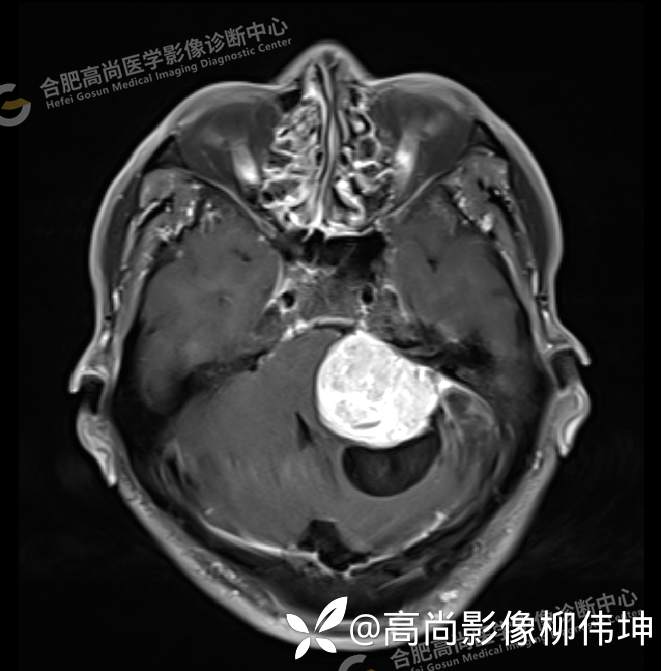

患者,男,58岁,头晕、行走不稳半年余。当地医院CT检查示左侧小脑区囊性灶,为进一步明显病情,遂来本中心进一步检查。

颅脑MRI平扫+增强示:双侧大脑半球对称,左侧桥小脑角区可见一团块状异常信号影,边界尚清,病灶与小脑幕宽基底附着呈“D”字征,上缘指状伸入幕缘上生长,病灶大小约43mmx42mmx36mm,其内信号不均,T1WI呈等低信号,T2WI呈混杂等高信号;FLAIR呈高信号,内可见条状低信号影,DWI呈稍高信号,ADC呈低信号,弥散轻度受限,病灶后方左侧小脑半球区可见一大小约33mmx16mm的弧形长T1长T2信号影,FLAIR呈低信号,其周围可见片状高信号影,相邻桥小脑角增宽。脑桥、小脑蚓部,小脑半球、第四脑室、环池受压变形,向右侧偏移,四脑室明显变窄,增强扫描病灶可见不均匀明显强化,邻近脑膜可见线样强化改变。其后方囊性灶未见异常强化。邻近骨质未见明显异常信号。左侧内听道显示正常;左侧中耳乳突内可见不规则性长T1长T2信号影。余脑实质内未见局灶性信号异常。双侧侧脑室及第三脑室体积增大,中线结构居中。矢状面示垂体形态大小正常,未见局灶性异常信号。

1.左侧桥小脑角区占位伴周围囊变,轻度梗阻性脑积水;考虑左小脑幕脑膜瘤。